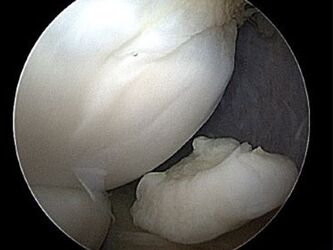

OSTEOCHONDROSIS DISSECANS

Die Osteochondrosis dissecans (OD) bezeichnet eine umschriebene Knochenläsion direkt angrenzend an den Gelenkknorpel der Oberarmrolle des Ellenbogengelenkes (Capitulum humeri). Die Erkrankung verläuft in Stadien und es kann am Ende zu einer Herauslösung des betroffenen Knorpel-Knochen-Fragmentes kommen.

Betroffen sind hauptsächlich aktive Kinder und Jugendliche. Die Entstehung ist noch nicht gänzlich geklärt. Wiederkehrende starke Belastungen (Werfen) gelten als mögliche Ursache. Zu einem der Osteochondrosis dissecans ähnlichem Krankheitsbild führt der Morbus Panner, eine Durchblutungsstörung des Capitulum humeri die im Kindesalter auftreten kann.

Die Betroffenen geben meist belastungsabhängige Schmerzen des Ellenbogens zum Beispiel beim Sport an. Da diese Schmerzen größtenteils unspezifisch sind, dauert es häufig recht lange, bis diese Erkrankung diagnostiziert wird. Die Diagnose erfolgt hauptsächlich über Röntgen- und kernspintomographische Untersuchungen. Im späten Stadium bei herauslösen von Fragmenten kann es zu Blockaden und Einklemmungen kommen.

Die Therapie richtet sich nach dem Alter des Betroffenen sowie dem Stadium der Erkrankung. Der konservative Therapieansatz umfasst eine deutliche Reduktion der Belastung des Gelenkes zum Beispiel durch ein konsequentes Sportverbot. Zusätzlich sollte ein Vitamin D3-Mangel ausgeschlossen werden.

Schreitet die Erkrankung trotz konsequenter konservativer Therapie fort oder liegt ein fortgeschrittenes Stadium der Erkrankung vor, ist eine operative Therapie zu empfehlen. Mit Hilfe einer Arthroskopie (Gelenkspiegelung) wird das Gelenk mit dem erkrankten Areal untersucht und kann befundabhängig sowohl direkt als auch indirekt von außen über Bohrungen behandelt werden. Durch die Bohrlöcher können Stammzellen und Wachstumsfaktoren in das abgestorbene Knochenareal eindringen und dieses wieder aufbauen. Die Knorpelschicht ist mit einer Knorpelglättung, Refixierung des Fragmentes bis hin zu Knorpel-Knochen- oder Knorpelzelltransplantation behandelbar.

Die Nachbehandlung richtet sich nach den Erfordernissen der Regeneration des Gewebes und ist in den meisten Fällen durch eine geschützte Phase von ca. 6 Wochen ohne wesentliche Belastung des Gelenkes gekennzeichnet.

Bild Fragment Ellenbogen bei Osteochondrosis dissecans

Fragment Ellenbogen bei Osteochondrosis dissecans